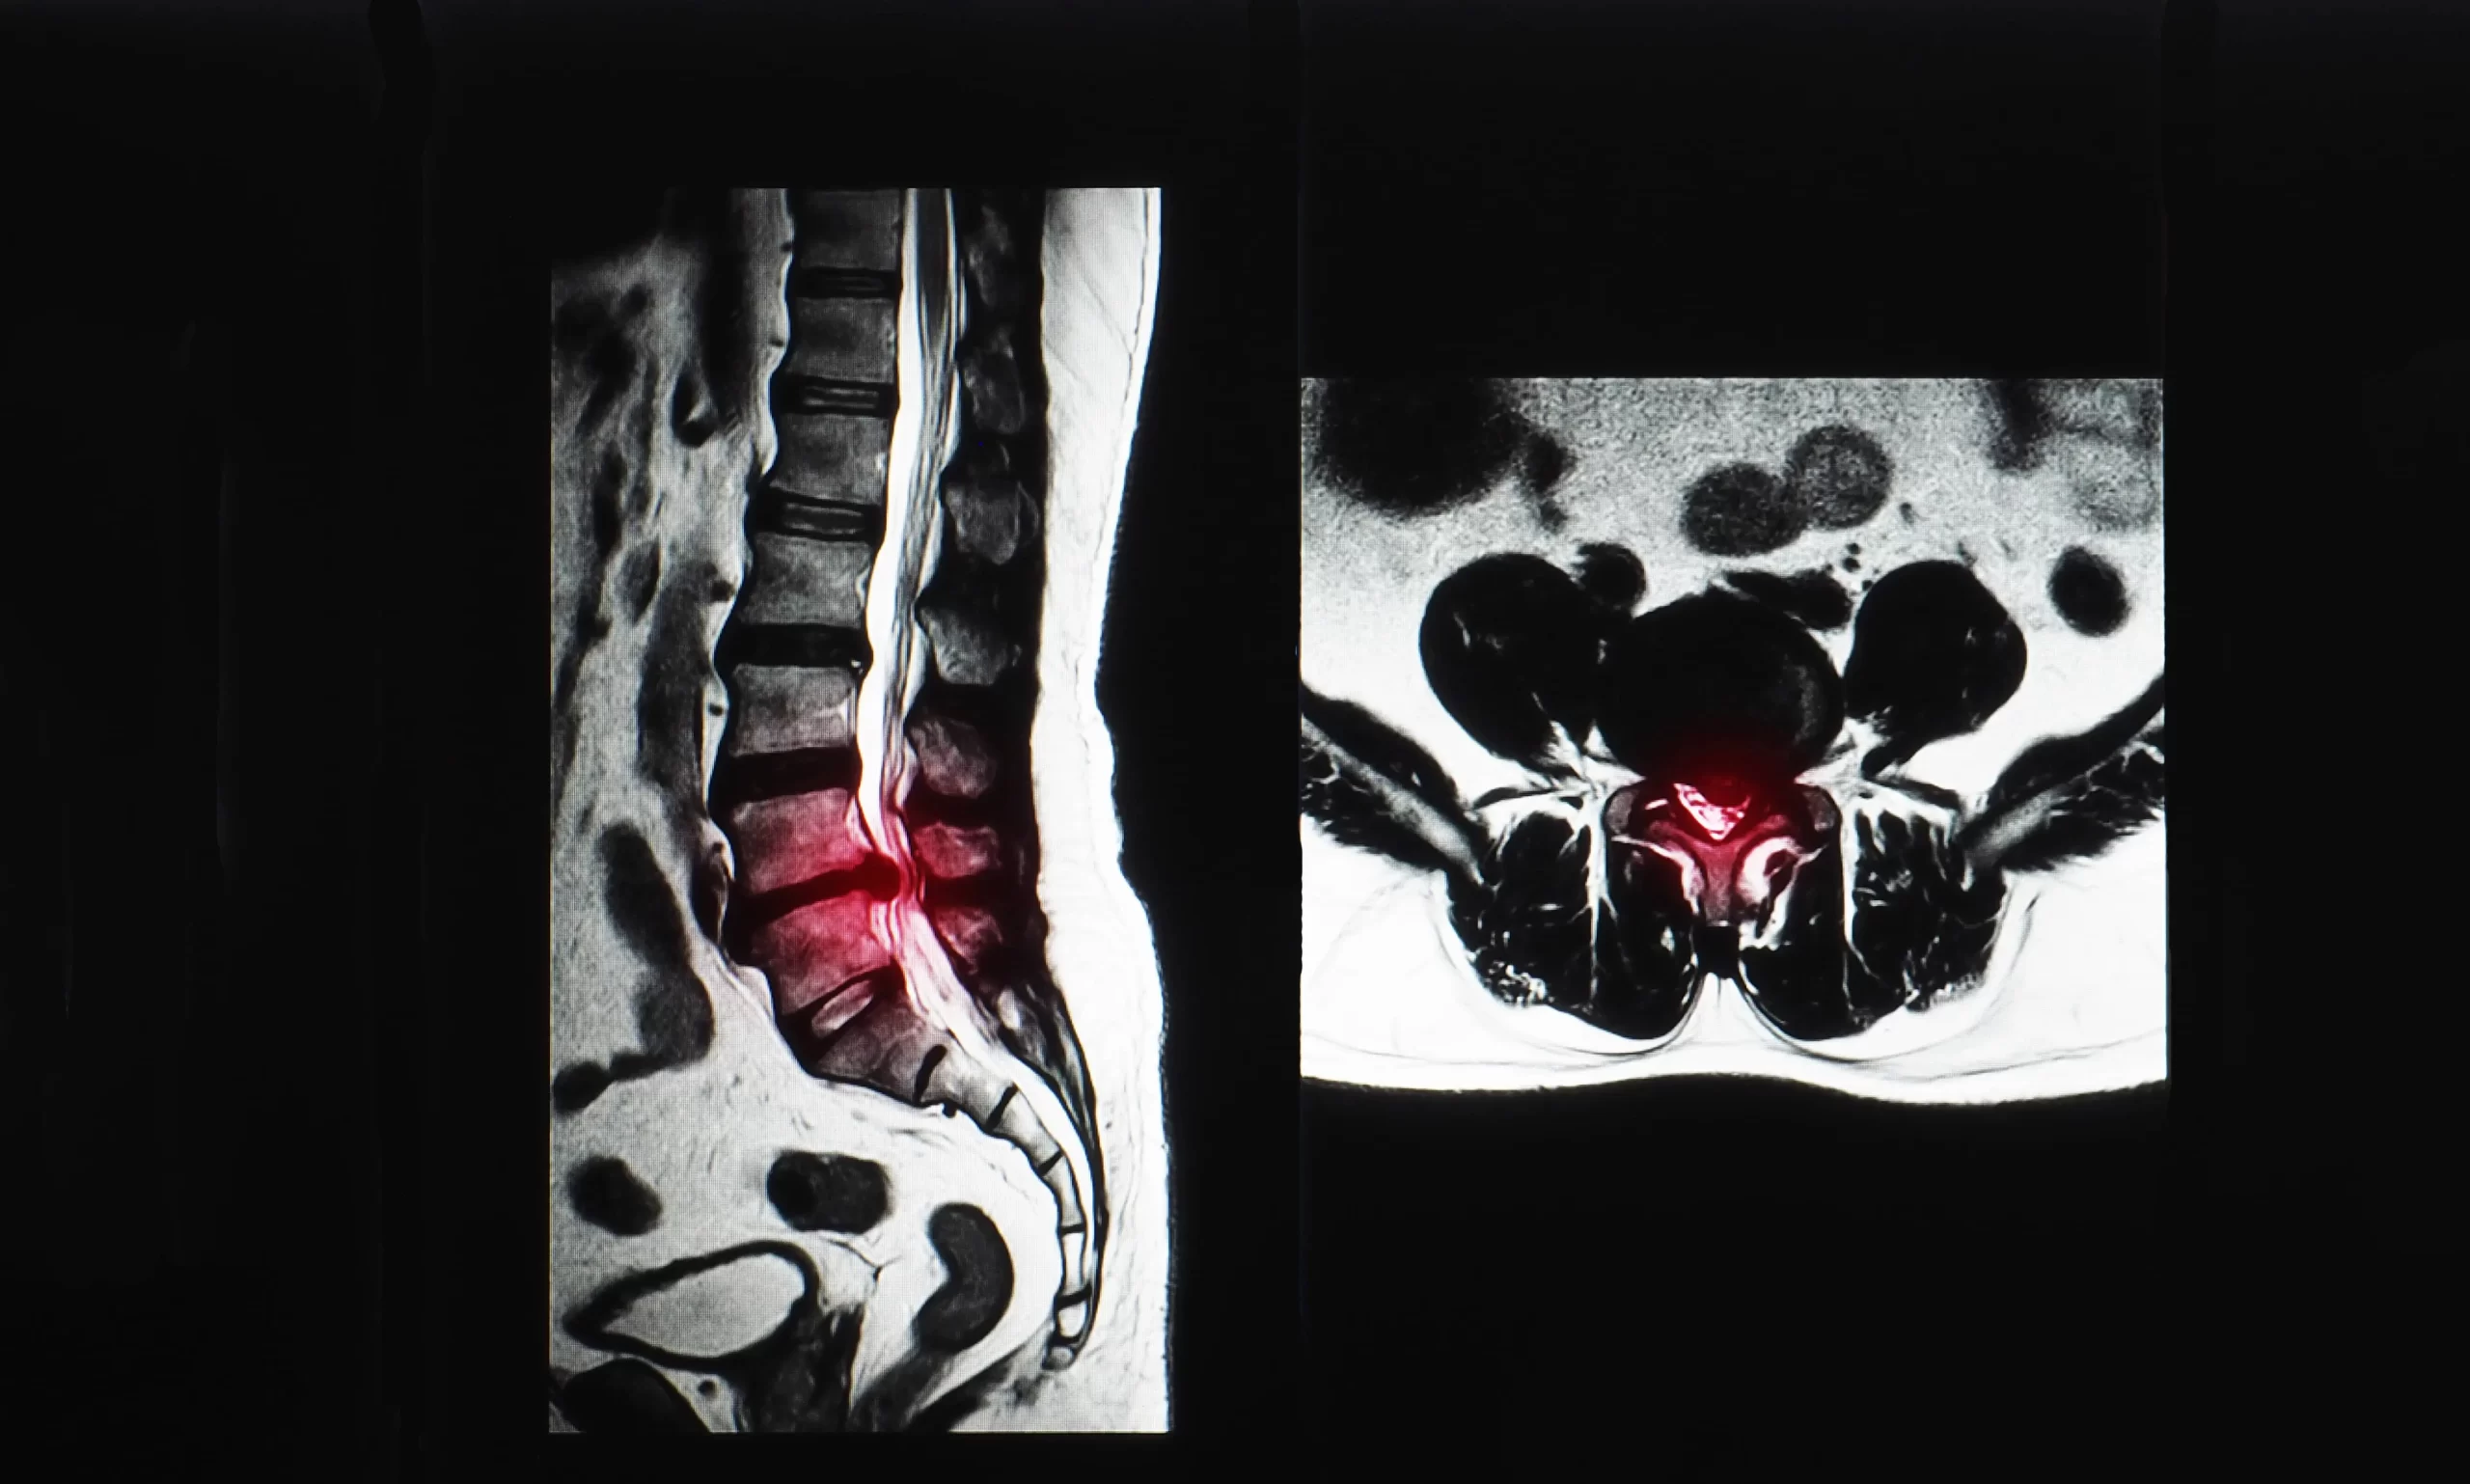

Hastalığın tanısında; klinik muayene bulgularının yanı sıra röntgen, MRI (Manyetik Rezonans), CT (Bilgisayarlı Tomografi) sıklıkla kullanılır. EMG dediğimiz sinirlerin elektro fizyolojik tetkiki gerekebilir. Tüm tetkik ve bulgular sonucunda ortaya çıkan tablo kişinin bel fıtığı hastası olup olmadığını ortaya koymaya yardımcı olur. Bel grafileri (x-ray), bel ağrısı şikayeti ile sağlık kuruluşlarına başvuran hastalarda kullanılabilecek ilk radyolojik görüntüleme yöntemidir. Genel olarak bu filmlerin çekilmesi 3 yönden gerçekleştirilir ve bel grafileri sayesinde hastanın omurlarının dizilimi, olası kırıklar ve dejeneratif değişiklikler tespit edilebilir.Omurganın kemik yapısının incelenmesindeki en duyarlı tetkik bilgisayarlı tomografidir (CT). Tomografi görüntüleri sayesinde kalsifiye olmuş ya da fıtıklaşmış diskler tespit edilebilir.Bir diğer radyolojik görüntüleme yöntemi olan manyetik rezonans görüntüleme (MRI), bel fıtığından şüphelenilen hastalarda altın standart tanı aracı olarak kabul edilir. Tanısal doğruluğu yaklaşık olarak %97 olan bu işlem, yumuşak dokuyu da ayrıntılı olarak görüntüleyebilmesi nedeniyle oldukça duyarlıdır.